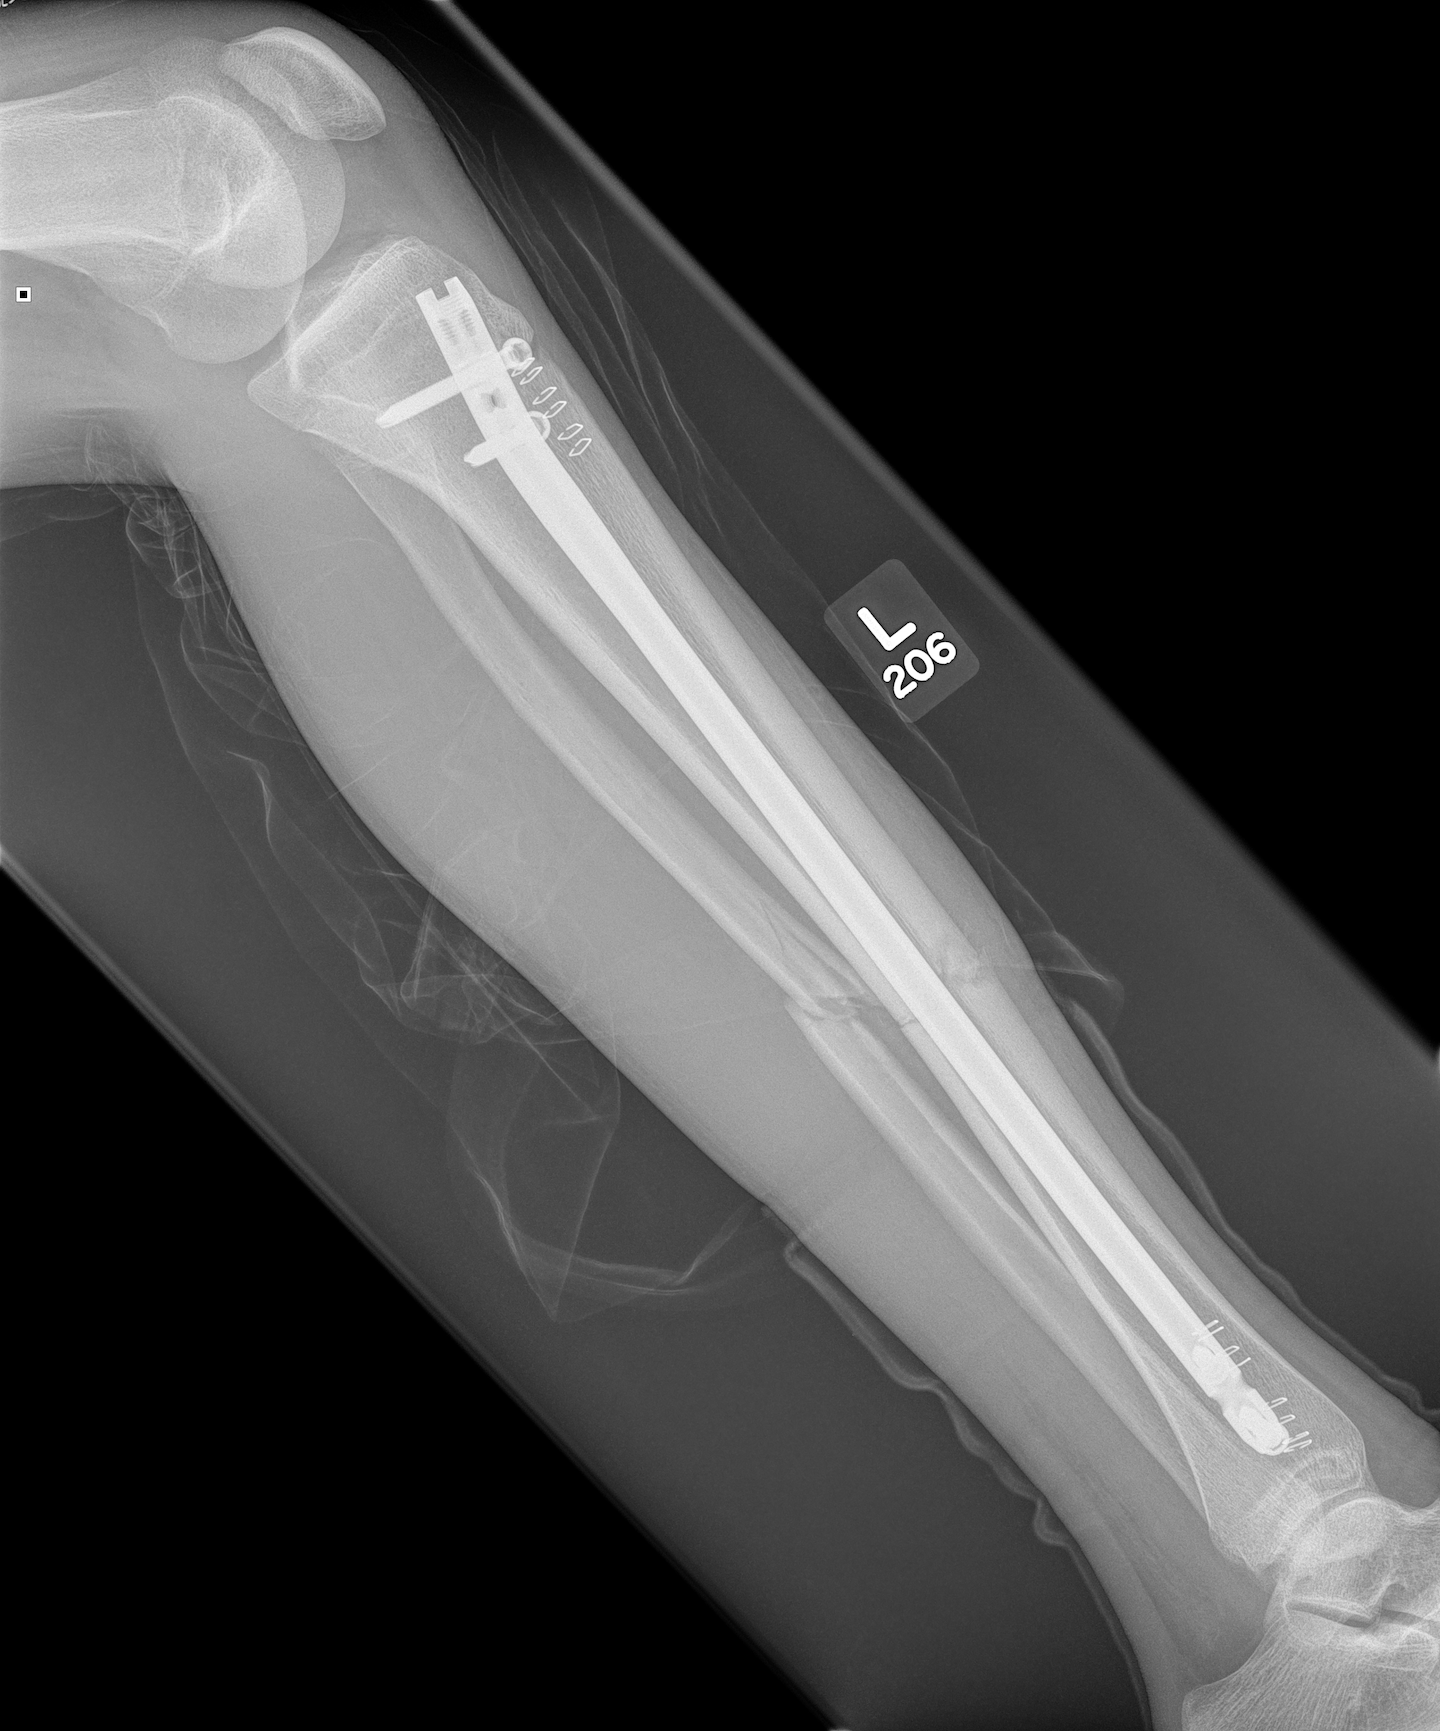

1.  IMN Tibia

Tibial Nail 1Tibial Nail 2

Segmental shaft fractures

Segmental tibia 1Segmental tibia 2

Corey et al J Orthop Trauma 2018

- 95 treated with IMN

- nonunion rate 10%

https://pubmed.ncbi.nlm.nih.gov/29432320/